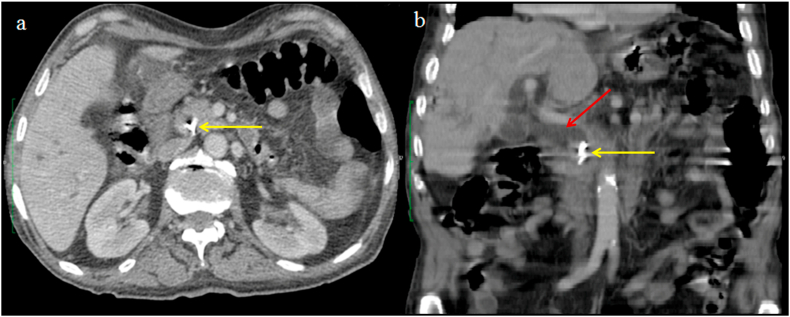

An 83-year-old man, known case of diabetes mellitus taking insulin, presented with severe abdominal pain, nausea, and jaundice for 3 days. Past surgical history included uneventful laparoscopic cholecystectomy for cholelithiasis 8 years back, with intraoperative cholangiogram showing clear bile ducts. The patient has episodic right upper quadrant abdominal pain for the past six months. The abdominal pain lasted for less than 6 hours without jaundice or fever. However, he has developed jaundice since three days. On physical examination, he was febrile (temperature of 38.5 °Celsius), had tachycardia, icterus, and tenderness in the right upper quadrant. Laboratory investigations revealed leucocytosis and elevated liver enzymes: alanine aminotransferase (ALT)260 U/L (N 7–40), aspartate aminotransferase (AST) 240 U/L (N 7–40), gamma-glutamyl transferase (GGT) 330 U/L (N 7–32) and a total bilirubin level of 102 μmol/L (N 5.1–17) with a direct bilirubin level of 91 μmol/L. Contrast-enhanced computed tomography of the abdomen (CT) showed intra and extrahepatic ducts dilatation secondary to a hyperdense object located in the distal common bile duct (CBD) as shown in Fig. 1. Based on clinical symptoms, laboratory results, and tomography findings, the diagnosis of cholangitis was confirmed. Broad-spectrum antibiotics and fluid resuscitation were started immediately and an urgent endoscopic retrograde cholangiopancreatography (ERCP) was performed. The ERCP revealed intra and extra ductal dilatation secondary to an occluding stone in the CBD formed around the surgical clip (Fig. 2). An endoscopic sphincterotomy was performed and the clip was removed. The patient was discharged after 6 days of hospitalization. At the last follow-up of one year after his admission, the patient is symptom-free with normal liver enzymes and abdominal CT.